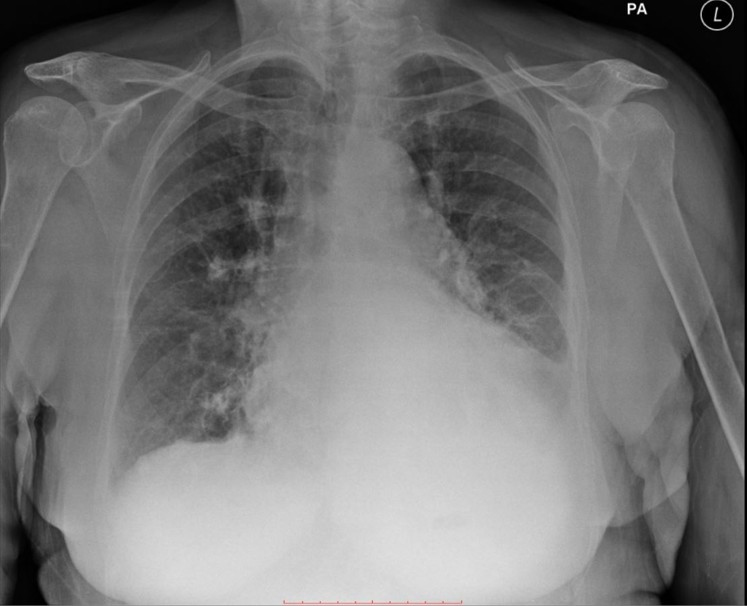

FRCR cases are exam-style radiology cases that simulate the FRCR 2B exam experience. Unlike textbooks, case-based practice allows you to apply knowledge in realistic scenarios, interpreting imaging, forming differential diagnoses, and practising structured reporting.

Understand the FRCR 2B exam format, including short cases & oral exams. Learn what candidates are assessed on & how to prepare effectively.

Preparing for the FRCR 2B exam requires more than reading textbooks or reviewing notes. Success depends on developing structured reporting skills, improving pattern recognition, and becoming confident in exam-style case interpretation.